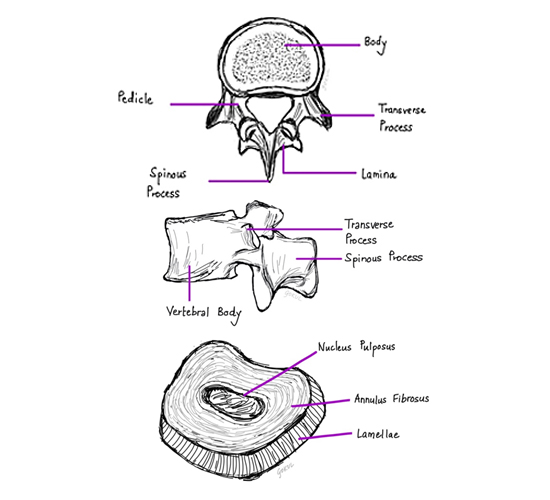

The spine (vertebral column) is made up of several bones called vertebrae which are stacked one upon another. Each vertebra is joined to the vertebrae above and below by two pairs of joints called the facet joints situated on the two sides. The typical vertebra has a solid body in front and two plate-like structures on two sides at the back called laminae. The laminae meet in the midline to form a protrusion, the spinous process, which can be felt through the skin of the back. On the two sides each lamina is joined to the body of the vertebra by a short bony stud called the pedicle, thus completing a bony ring. These rings inside each vertebra join together to form a tube called the spinal canal through which passes the spinal cord and the nerve roots.

A small gap, the intervertebral foramen, is present in between the adjacent pedicles for the passage of the nerve roots. These nerve roots are the connections that carry all sensations from the body to the brain and also bring commands from the brain to muscles resulting in movement. In between two adjacent vertebral bodies there is a strong rubber like tissue (Cartilage), resembling a washer, called the intervertebral disc. The nerve root in the intervertebral foramen lies just behind the disc. A disc has a stronger outer part called the annulus fibrosus and a softer jelly-like central part called the nucleus pulposus. When a patient has a prolapsed disc, the central soft part of the disc bulges out and can press on the nerve root/s.